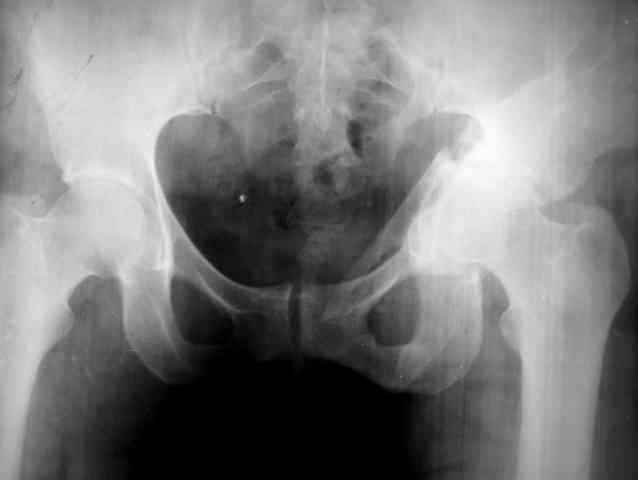

Ув.коллеги, нужен совет по представленному случаю. Пациентка 50лет. В

2003 году в результате дтп получила перелом вертлужной впадины. 1.5

месяца находилась на скелетном вытяжении, в дальнейшем до 10 месяцев

после травмы ходила без опоры на конечность. Вернулась к труду, но в

2006 году перешла на инвалидность и была поставлена в областную

очередь эндопротезирования. В данный момент уже находится в

отделении, но, судя по рентгенограммам и данным КТ, сращения на

уровне перелома не произошло. Что предпочесть?

Вложение не в текстовом формате было извлечено…

Имя     : фас.jpg

Тип     : image/jpeg

Размер  : 8801 байтов

Описание: отсутствует

Url     : http://weborto.net:8080/pipermail/ortho/attachments/20090324/8863a2fd/attachment-0011.jpg